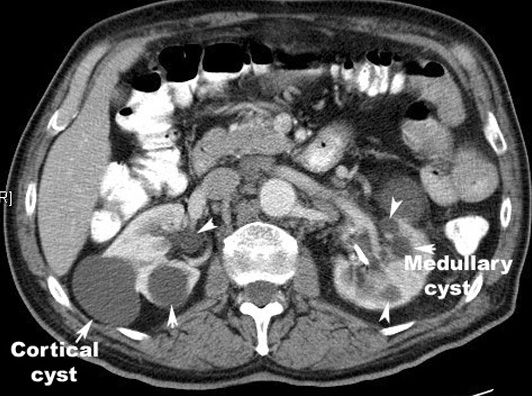

Polycystic kidney disease: A positive test requires:

• in patients younger than 30 years of age, at least two cysts (unilateral or bilateral)

• in patients 30-59 at least two cysts in each kidney

• in patients over 60, four or more cysts

Kidneys are large in polycystic kidneys.